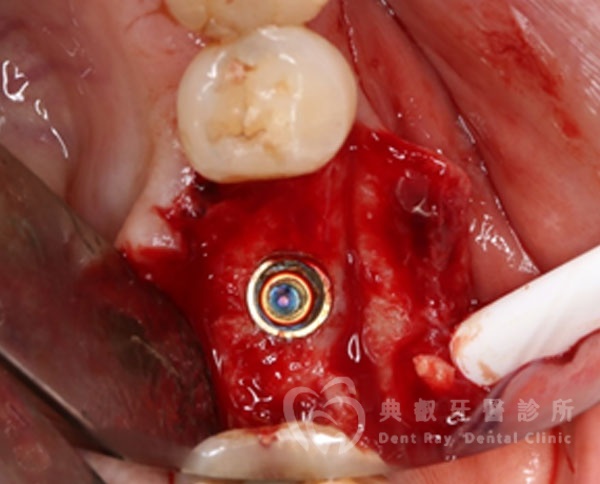

植牙案例一

植牙案例